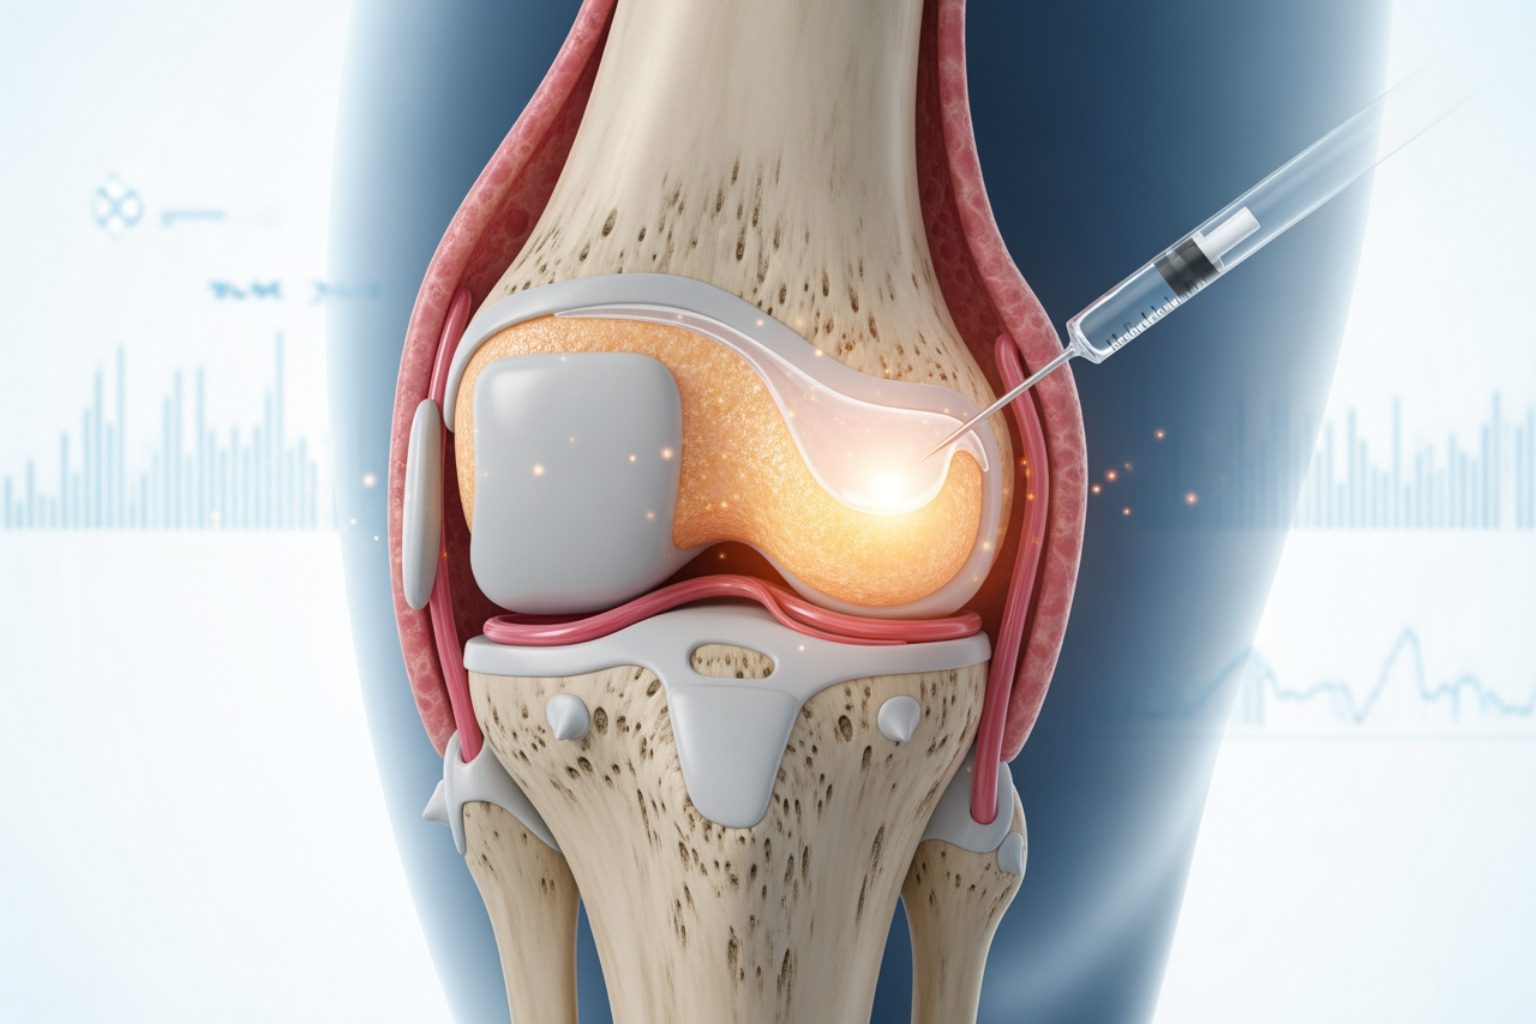

Therapeutic Injections for the Knee

Injections deliver medication directly into the knee joint for more potent relief.

- Corticosteroid injections provide powerful, short-term anti-inflammatory relief lasting several weeks to months. Use is typically limited to a few times per year.

- Hyaluronic acid injections aim to lubricate the joint, but research on their effectiveness is mixed.

- Platelet-rich plasma (PRP) uses your own blood's concentrated platelets to promote healing. Evidence is still developing for its use in knee OA.

- Stem cell injections are an experimental treatment aiming to regenerate cartilage. More research is needed to confirm their safety and effectiveness.